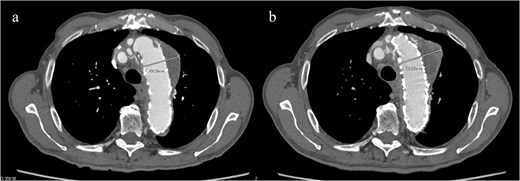

CT revealed no endoleak, but the aneurysm had enlarged to a diameter of 56 mm (Fig. 1b). Three-dimensional CT revealed straightening and proximal migration of the FET (Fig. 2). No clear signs of pulmonary parenchymal hemorrhage or findings suggestive of the mass were reported. Laboratory tests indicated mild anemia, with a hemoglobin of 9.7 g/dL and hematocrit of 29.0%. No infectious or inflammatory diseases that could cause hemoptysis were identified.

(a) Three-dimensional CT image 1 year after total arch replacement with a FET. (b) Three-dimensional CT image 2 years after total arch replacement with a FET demonstrating straightening and migration of the FET.